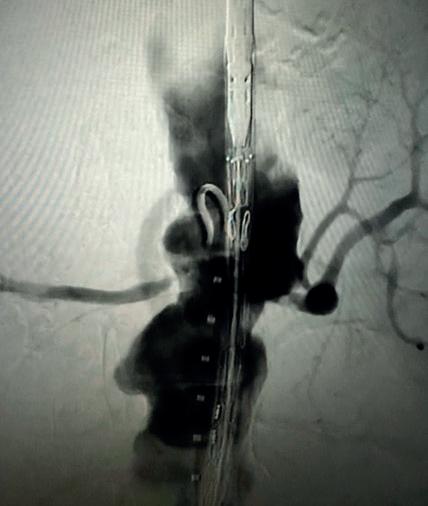

Case 1: The Shockwave L6 device in the setting of FEVAR and complex iliac stenosis

An 82-year-old man with a history of coronary artery disease (CAD), hypertension, hyperlipidemia, and peripheral arterial disease (PAD) presents with rest pain as well as

a large pararenal abdominal aortic aneurysm (AAA). His computed tomography angiography (CTA) revealed very dense and highly diseased iliac vessels with calcium deposition along most of the bilateral common iliac distribution.

The minimum luminal diameter (MLD) of the common iliac arteries measured roughly 4.5mm; however, the

healthy reference vessel diameter (RVD) was 9.5mm. He would require a fenestrated repair of the AAA along with complex iliac stenosis treatment, and extensive bilateral common femoral endarterectomies.

Further, we were concerned we would not be able to advance the 19F fenestrated graft. The endograft was prepared, and then both femoral arteries were exposed. We attempted delivery of the endograft via the right common iliac access. This failed. We then attempted delivery on the contralateral side. Despite multiple attempts, we made little progress. A 10x30mm Shockwave L 6 catheter was selected, and a total of 150 pulses were delivered to each iliac artery at just 4atm. This not only allowed for the delivery of our FEVAR graft but also the full unrestricted expansion of the endograft limbs in the common iliac arteries.

At the completion of the AAA, we took extra time to perform endarterectomies of the deep femoral arteries. His completion CT scan revealed a good seal of the AAA, patency of the renal fenestrations and unrestricted flow to the bilateral femoral arteries.

This is a great example of how IVL can be used as a standalone therapy without the need for adjunctive treatment.

MLD = 4.5mm RVD = 9.5mm IVL Device Choice = Shockwave L6 10mm

Figure 1. Pre-procdural CTA Figure 4. Graft delivery Figure 1. Pre-procedural angiogram Figure 2. Pre-procedural angiogram Figure 5. Final angiogram Figure 2. IVL treatment angiogram Figure 3. Post-IVL angiogram Figure 6. Post-procedural CTA Figure 3. Final angiogram